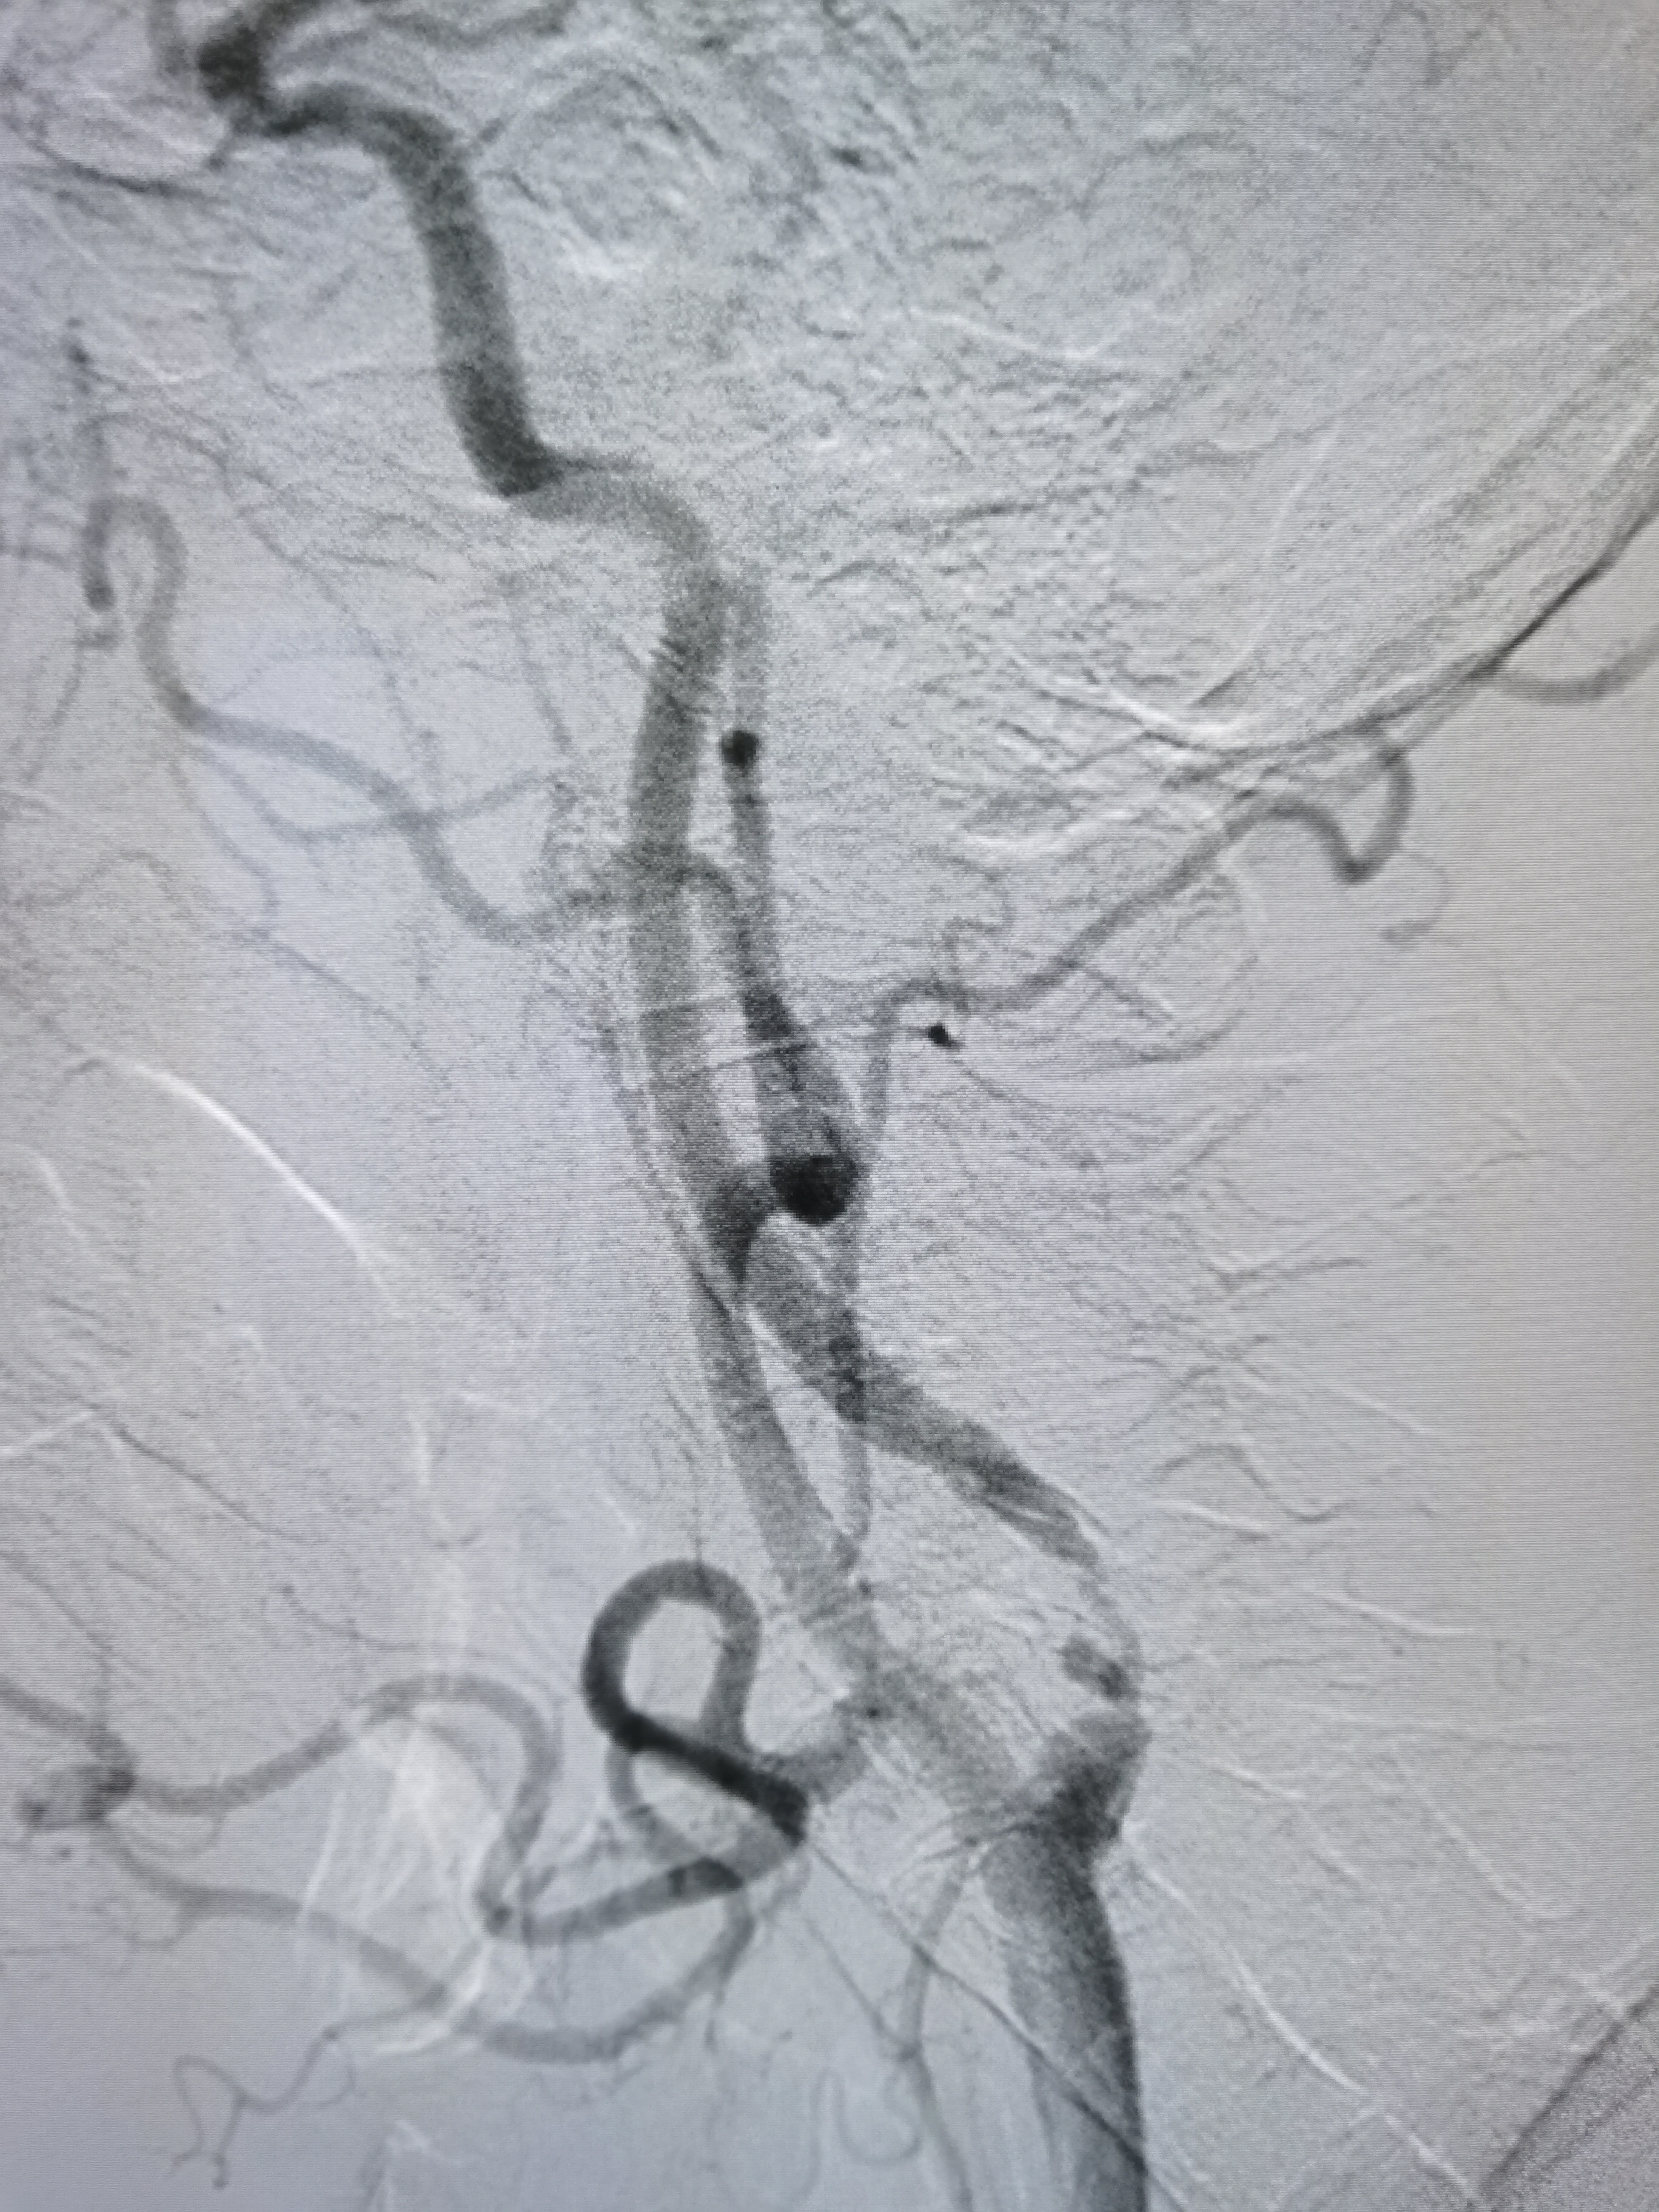

支架释放后狭窄解除

左侧胚胎型大脑后动脉,颅内血流明显改善。

支架位置形态满意,撤出保护伞,结束手术。

术前术后对比